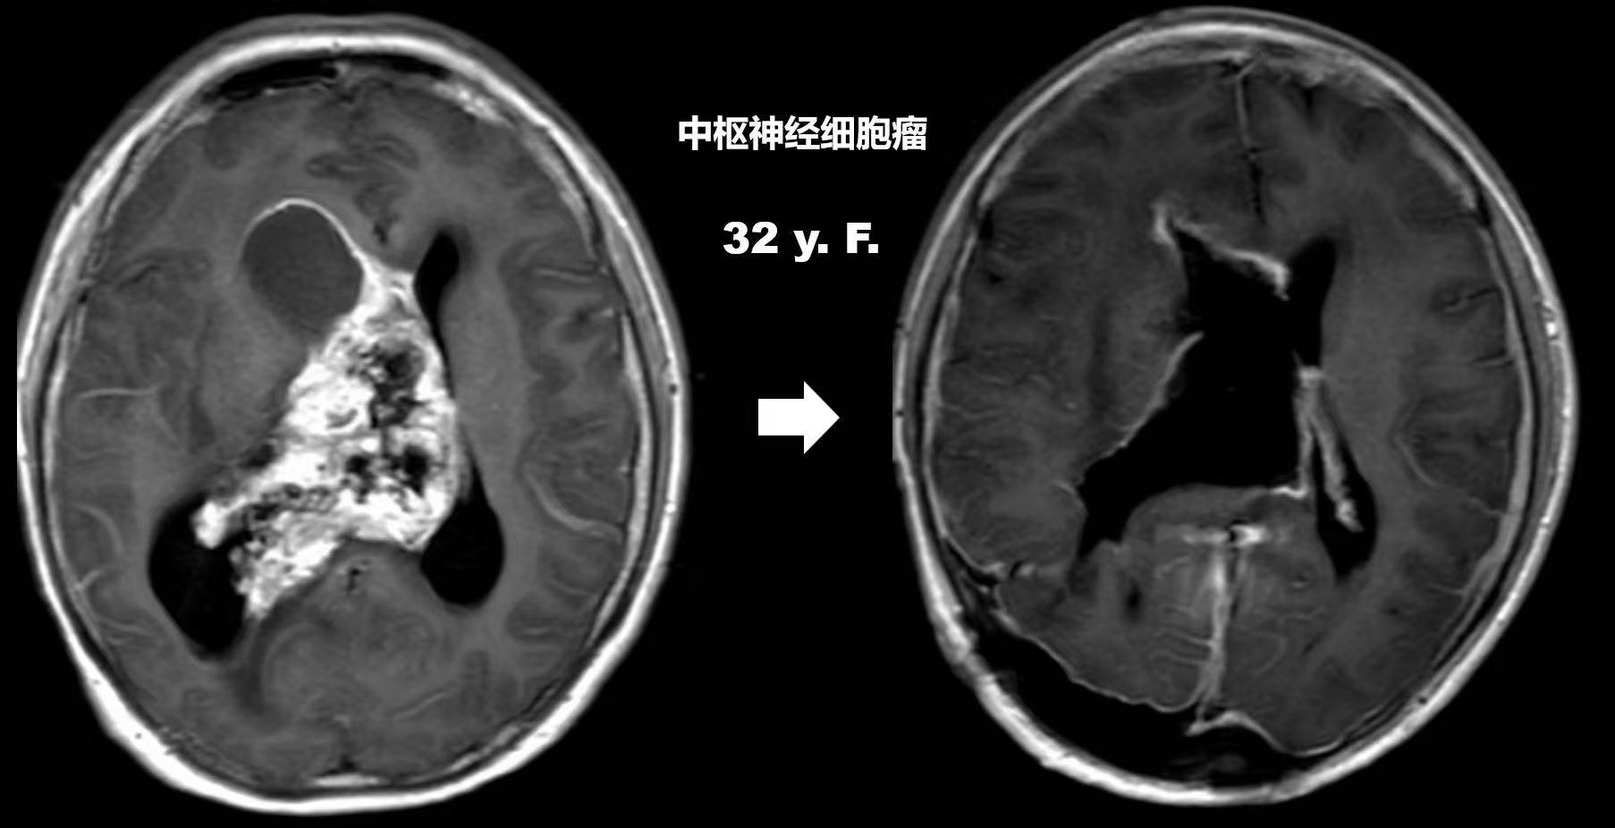

为寻求进一步诊治,阿玲和老公决定前往北京求医。在北京的医院,阿玲被诊断为中枢神经细胞瘤,这是少见的脑肿瘤。令人吃惊的是,阿玲脑室内的这颗肿瘤接近成人拳头大小。因为肿瘤已几乎将整个脑室腔占满,且其周围全部是重要神经功能结构,如不及时进行手术,将进一步压迫这些区域;同时,这种低度恶性的肿瘤,手术切除的程度直接会影响患者的预后。“保守治疗吧!”出于同样的理由,北京的医院也不建议阿玲手术。从此,阿玲和丈夫开始了漫长的求医路。

阿玲只好前往四川成都的医院进行放疗。在成都待了一个半月,放疗了二十次 ,阿玲的状态好多了,意识也比较清晰了。但好景不长,阿玲出院后没多久,又开始出现记忆力下降、视力模糊、耳鸣等症状,时常把前几天的事当做刚发生的事,还反复提出很多重复问过的问题。家人一开始以为是放疗后带来的影响,所以也没太注意,就这样日复一日。直到今年2月,阿玲又出现呕吐、嗜睡、记忆错乱等症状,于是又去当地医院做了复查,这一次的检查结果相对于上次检查肿瘤又进一步增大,已接近10公分了。

“肿瘤不断长大,导致脑室内的脑脊液循环受阻,形成颅内‘堰塞湖’,颅内压不断升高,随时会危及生命。”接诊的杜世伟教授说,当务之急是立刻进行手术治疗。但肿瘤巨大、血供丰富,与脑室壁粘连明显,要想完全分离、切除肿瘤,充满了挑战。杜世伟教授说,脑室内“地形”复杂,血管、神经组织密布,手术中稍有不慎就有可能大出血或是造成严重的功能损伤,加上阿玲还很年轻,因此,如何在切除肿瘤的同时,最大程度地保护脑功能是手术的最大难点。

和大外科手术的酣畅淋漓不一样,脑科手术更像一种“蚂蚁啃骨头”的工程,亦像在“钢丝绳上舞蹈”。医生要避开各种神经、血管,一点点把肿瘤抠出来。杜世伟教授使用国际最先进的神经外科显微镜在患者脑表面安全区域打开一个直径约1.5厘米的造瘘口,然后使用显微器械一边分离肿瘤与脑组织的界限,一边将细小血管电凝止血。其间结合术中超声、术中电生理监测、术中导航、神经内镜等多技术协作,历经10个小时,最终成功无残留地干掉了肿瘤。

据悉,中枢神经细胞瘤是生长在侧脑室和第三脑室的小细胞神经元肿瘤,以中青年多见,平均发病年龄在30岁左右。由于肿瘤位置深,早期症状不明显。当它持续生长引发阻塞时,患者会出现持续头痛、频繁呕吐等症状。杜世伟教授提醒,中枢神经细胞瘤早发现早治疗是关键,一旦出现不明原因的头痛呕吐,应及时到医院就诊,避免贻误病情。